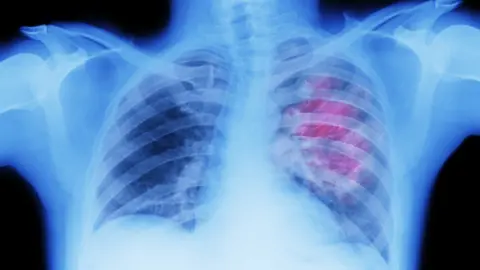

Lung cancer patient says earlier screening might have made a difference

BBCA County Armagh man with stage four lung cancer has backed calls for a screening programme for the disease to be rolled out across Northern Ireland.

Cancer Research UK have said there is an urgent need for the introduction of a targeted-screening programme for lung cancer in Northern Ireland.

Lung cancer is the leading cause of cancer death in Northern Ireland with about 1,000 dying from the disease each year, according to the charity.